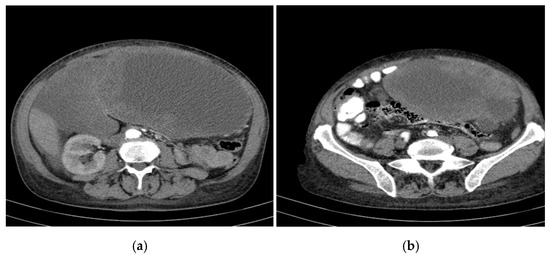

Over the course of 55 months of treatment with imatinib, the patient was monitored by imaging, exhibiting a stable disease course with no significant tumour progression and some evidence of partial regression of specific lesions. CT appearance at 12 months of treatment with imatinib is presented in Figure 3. The following key observations emerged from the serial CT evaluations:

Figure 3.

CT appearance at 12 months of treatment with imatinib at different abdominal levels.

- Hepatic tumour stability: Multiple large cystic hepatic lesions remained stable in size throughout the monitoring period, with no significant new secondary lesions developing. The largest hepatic cystic tumours persisted in segments IV, VI, and VIII, with maximum dimensions of ~8 cm, without major structural changes.

- Regression of extrahepatic lesions: Initial gastric and peritoneal lesions, including a cystic formation in the anterior gastric wall and ascitic fluid, regressed significantly by month 14 and did not reappear in later scans. The left inguinal hernia, although noted consistently, remained unchanged, without complications.

- Emergence of new findings without aggressive progression: A subcapsular nodule (3.5 × 2 cm) in Morrison’s space was identified during month 41, remaining stable without concerning enhancement patterns. A pseudo-nodular perfusion anomaly in segment VIII was noted but was attributed to pressure from the large cystic tumour rather than neoplastic progression. Mild gastric antral wall thickening developed later (by month 49), with a maximum thickness of 14 mm, but remained stable thereafter, with no associated adenopathy or signs of malignant transformation.

- Absence of significant distant metastases or new systemic involvement: Throughout the entire monitoring period, there were no newly detected secondary metastatic lesions in the thoracic, abdominal, or pelvic regions; no significant adenopathy was identified; and there was no recurrence of ascitic fluid beyond a mild amount in the early monitoring phases.